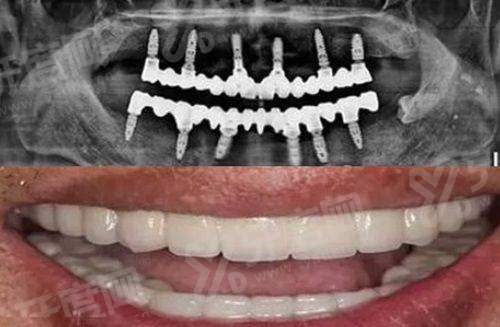

1、大连齿医生口腔医院引进了口内扫描与 CBCT 联合建模系统,术前就能在电脑上模拟出牙齿种植的三维路径,避开重要的神经和血管,这不是靠手感猜,而是靠数据算。

2、通过制作个性化的 3D 打印手术导板,徐奥翔医生在手术时能严格按照预定方案操作,将种植体植入的角度和深度误差控制在极小范围内,确保后期牙冠咬合舒适。

3、这种数字化技术特别适合那些对美观要求高或者口腔条件复杂的患者,它能大幅缩短手术时间,减少翻瓣创伤,让种牙过程变得更加可控和安心。